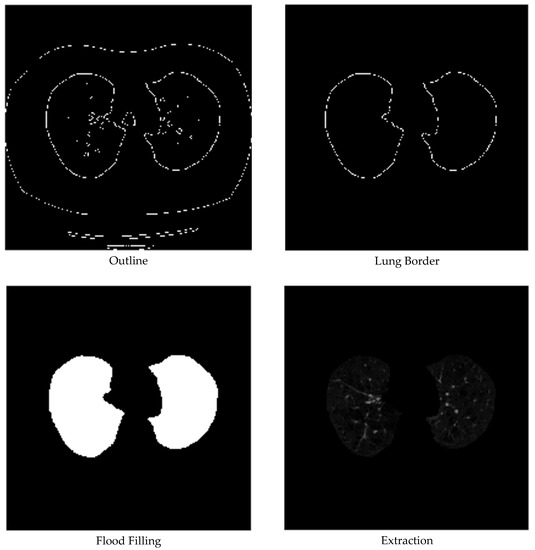

3.1. Data Pre-Processing